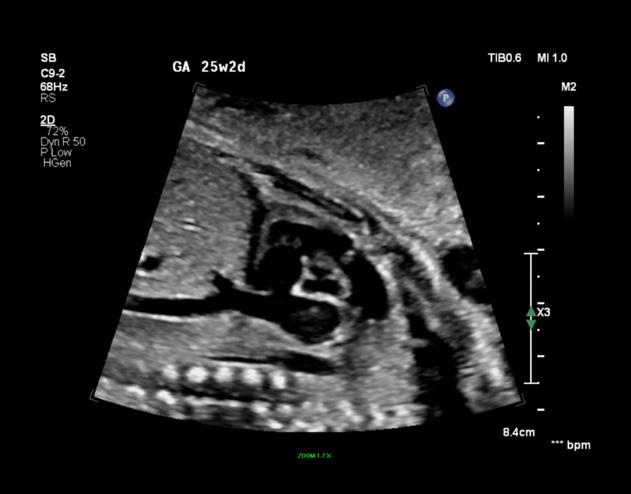

À la naissance, le nouveau-né est souvent bien coloré, rose, et ne présente pas de gêne particulière. Cependant, la présence d’un souffle cardiaque systolique, perçu dès l’auscultation en salle d’accouchement, attire l’attention. Un souffle d’apparition précoce nécessite une échocardiographie d’urgence.

Dans sa forme habituelle, la tétralogie de Fallot est bien supportée à la naissance et ne demande pas de traitement immédiat. Il est toutefois utile d’hospitaliser le nouveau-né en unité de réanimation pédiatrique pour une surveillance attentive. La cyanose, signe classique de la malformation, apparaît généralement plusieurs semaines après la naissance, d’abord lors d’efforts ou de colères. Au repos, elle reste modérée et difficile à détecter sans observation experte. La cyanose s’accentue progressivement, accompagnée de fatigue, gênant les acquisitions motrices de l’enfant.

Grand enfant et adulte

Il est rare de rencontrer une tétralogie de Fallot non opérée après l’âge de deux ans. Cela peut se produire dans des formes particulières ou dans des pays en voie de développement. Dans ces cas, le tableau clinique présente une cyanose plus ou moins profonde, accompagnée de fatigue et de dyspnée, limitant les possibilités d’effort en raison d’un manque d’oxygène et non d’une insuffisance cardiaque.

Étiologie, âge d’apparition et évolution

La tétralogie de Fallot est la conséquence d’une anomalie de cloisonnement du tronc artériel.

Anomalie chromosomique

Une microdélétion 22q11 serait présente dans près du quart des cas et serait à rechercher avant toute anomalie conotroncale. Ce type d’anomalie chromosomique est également associé au syndrome de Di George qui comporte fréquemment une atteinte cardiaque de type de tétralogie de Fallot.

Les autres anomalies chromosomiques fréquemment retrouvées sont le syndrome de Down ou trisomie 21, la trisomie 13, la trisomie 18 et le syndrome des yeux de chat.

La tétralogie de Fallot est une malformation décrite dans plusieurs syndromes, la plupart étant génétiques : syndrome-charge, syndrome d’alcoolisme fœtal.

Elle se forme principalement au cours du deuxième mois de la vie intra-utérine. Le diagnostic peut être posé avant la naissance grâce à l’échographie fœtale, avec une détection dans 70 à 80 % des cas (jusqu’à 100 % avec un échographiste de référence). Le plus souvent, il s’agit d’une découverte de novo, sans antécédent familial particulier.